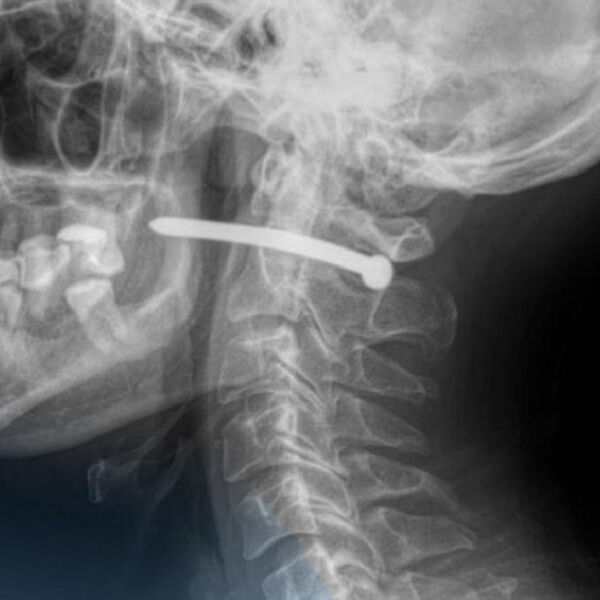

В Петропавловске 51-летний мужчина обратился в городскую больницу скорой помощи с ранением за ухом. Как выяснилось, во время ремонта он случайно получил травму — в него выстрелил гвоздь из пневматического пистолета.

Рентген показал, что металлический предмет прошел буквально в миллиметрах от шейного отдела позвоночника. Медики отметили, что мужчине невероятно повезло — жизненно важные органы и сосуды не были повреждены.